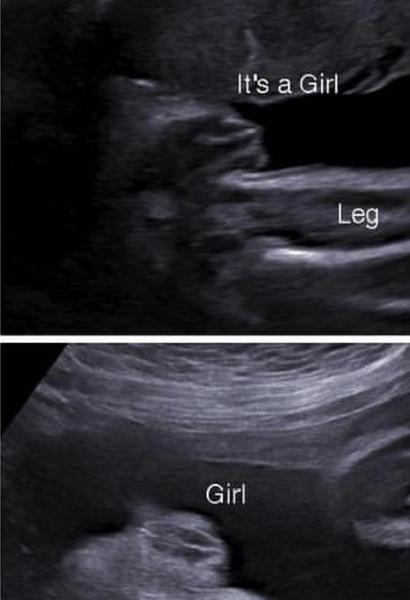

@nikkitas pokud to je pohlavní hrbolek,což asi jo,tak bych tipla holčičku 🙂

@marta6793 tak uvidíte, máte ještě nějaký ultrazvuk ? A fotku z 1. nebo z 2. scr. nemáte, kde by šlo vidět pohlaví ? Také máme potvrzenou holčičku (ve 22.tt), MUDr nám to napsala i do zprávy, už spoustu nakoupených věci tak doufám, že to tak zůstane. Ve 12.tt (genetika) - holka, v 15.tt- jiná MUDr spíše kluk ale koukla jen tak rychle ze spodu, ve 22.tt (genetika) ta samá MUDr z 1.scr. viděla pysky...docela dlouho to kontrolovala a říkala že už z toho kluk nebude.